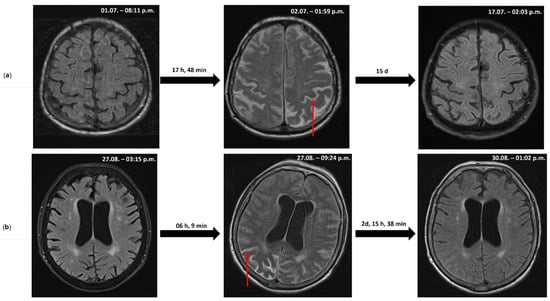

Acute Sulcal FLAIR Hyperintensity in Severe Tick-Borne Encephalitis: A Potential Prognostic Marker

Vincent Böhm, Bogdan-Andrei Ianosi, Caterina Kulyk, Franz Gruber, Maria Lorenz, Thomas Mitterling, Amadeus Hauser, Stephan Eger, Ulrike Köhl, Serge Weis, Sibylle Wimmer, Michael Sonnberger and Raimund Helbok

Life 2025, 15(11), 1655; https://doi.org/10.3390/life15111655 - 23 Oct 2025

(1) Background: To report two cases of severe tick-borne encephalitis (TBE) in elderly patients presenting with a previously undescribed subarachnoid T2/FLAIR hyperintensity on repeated MRI examinations, which may serve as an early imaging biomarker of disease severity. (2) Methods: Two unvaccinated 82-year-old patients (one male and one female) presented with acute encephalitis and required intensive care. Serial brain MRI, EEG, CSF analysis, and neurophysiological assessments were performed. (3) Results: Both patients showed rapid progressive neurological deterioration in the context of TBE, confirmed by elevated serum and CSF IgM and IgG titers. Early follow-up MRI revealed striking sulcal hyperintensities on T2/FLAIR sequences, interpreted as protein-rich subarachnoid inflammatory changes. These changes paralleled clinical worsening and resolved on follow-up imaging. The male patient developed meningoencephalomyeloradiculitis, remained comatose, and died from respiratory failure (the brain and spinal cord were examined postmortem). The female patient had meningoencephaloradiculitis with severe dysphagia and was discharged with a modified Rankin Scale score of four. Both patients demonstrated epileptiform EEG activity. The CSF analysis revealed markedly elevated total protein, lactate, tau protein, and CXCL13, as evidence of blood–brain barrier disruption and inflammatory neurodegeneration. (4) Conclusions: We describe acute subarachnoid T2/FLAIR hyperintensity in TBE as an imaging feature that may correlate with severe systemic inflammation and a poor prognosis. This radiological finding could serve as a potential early prognostic marker in TBE.